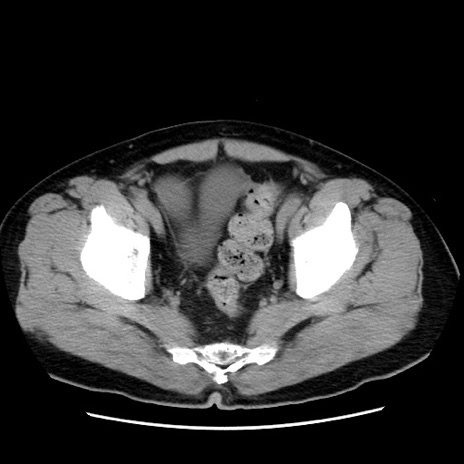

症例16(横断像)

【症例】 70歳代男性

【主訴】 腹痛、嘔吐

【現病歴】 約1ヶ月前より間欠的に腹痛と嘔吐あり、当院消化器内科を受診したところCTで多発する肝臓のLDAを指摘され、精査中であった。以降は消化器症状は安定していたが、2日前より嘔気と腹痛があり、同日より排便・排ガスが消失した。改善認めず、 本日、救急外来を受診した。

【既往歴】 大腸ポリープ切除後。

【身体所見】意識清明・会話良好、BT 36.3℃、BP 127/80mmHg、 P 80bpm、腹部:膨満あり、平坦・軟、上腹部正中および下腹部正中に圧痛あり、反跳痛なし、筋性防御なし。

【データ】WBC 7200、CRP 0.77